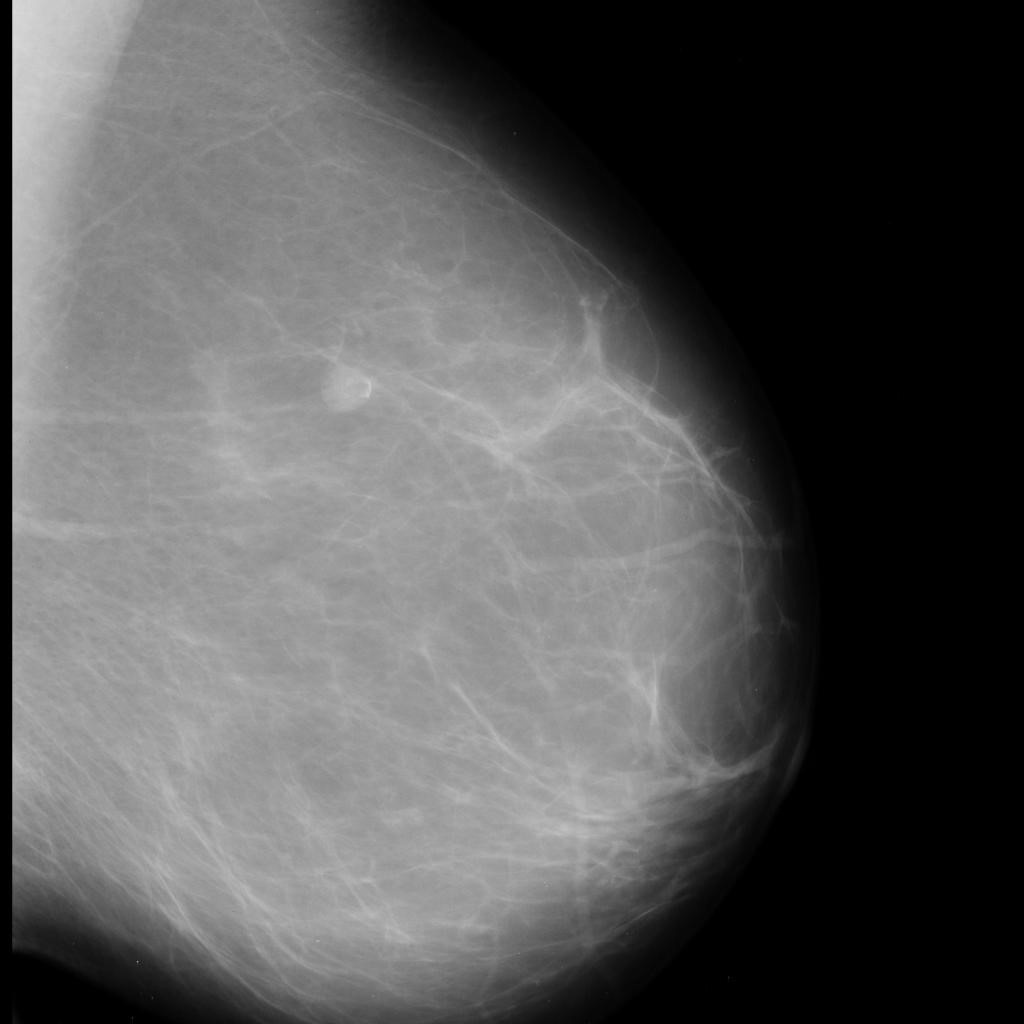

benign